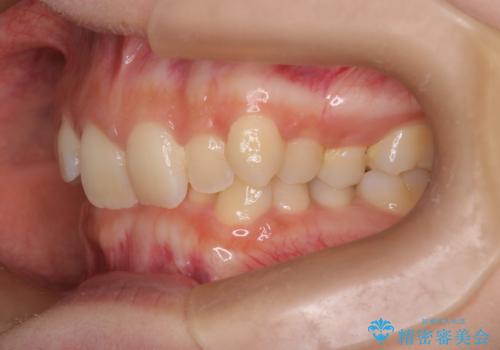

ディープバイト改善のためのインビザライン治療

- 患者様は、全体的な歯列のガタガタとディープバイト(深い噛み合わせ)を主訴として来院されました。診断の結果、ディープバイトを改善するためには、歯列全体の拡大が必要であると判断しました。治療には、透明なマウスピース型矯正装置「インビザライン」を使用し、歯を適切に拡大しながら歯並びを整える計画を立てました。治療期間はおおよそ2年を見込んで進め、最終的に見た目にも大きく変化をもたらすことを目指しました。

ディープバイトの治療には、奥歯の高さや前歯の位置に対する繊細な調整が必要です。本症例では、インビザラインによる歯列拡大を行うことで、噛み合わせを改善し、歯並び全体を整えました。治療過程では、歯間のスペースを確保するため、IPR(インタープロキシマルリダクション)を適宜行い、無理なく歯列の調整を行いました。治療後は、歯並びが大きく改善され、患者様の見た目にも大きな変化が現れました。インビザラインは透明で目立たず、治療中の見た目を気にされる患者様にも配慮した治療法です。